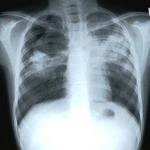

A kisebb visszaesés ellenére a baktérium által terjesztett fertőző betegségek közül világszerte még mindig a tuberkulózis okozza a legtöbb halálesetet - hangsúlyozták tudósok a tuberkulózis világnapja közeledtével.